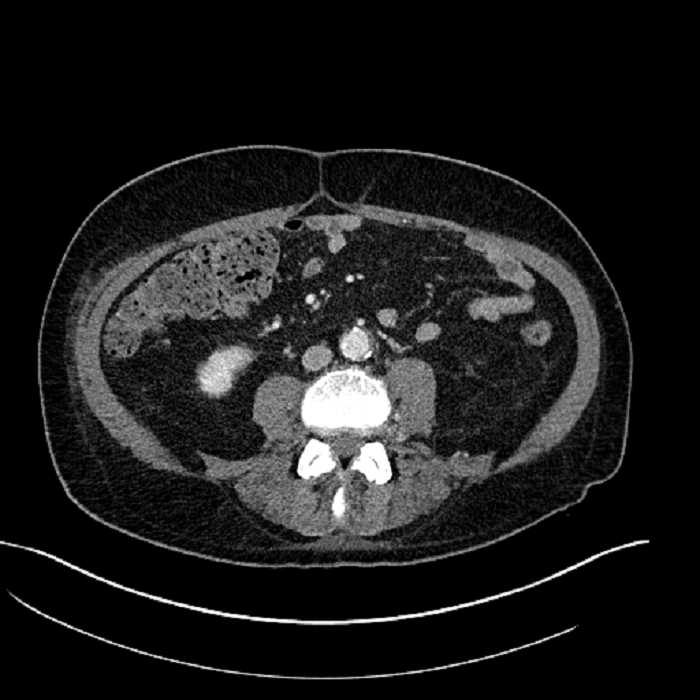

• Large fluid density structure in hepatic segments 7 and 8 measuring 10 x 7 x 7 cm with internal septation and circumferential ill-defined low density compatible with edema

• Peripherally enhancing subcapsular collections along the anterior margin of the left hepatic lobe measuring 3 x 1 cm and 2 x 1 cm

• Clearly marginated fluid density structure in segment 7 and several other scattered tiny hypodensities, which likely represent cysts

• Hepatic abscess

Acute sigmoid diverticulitis complicated by a small contained perforation and a large abscess in the right hepatic lobe. Additional small subcapsular abscesses along the anterior margin of the left hepatic lobe.

• The classic CT imaging appearance is a double target sign with internal low density surrounded by an internal enhancing rim (capsule) and a low density external rim (edema)

• Abscesses may be unilocular or multilocular

Hepatic abscess showing the double target sign with low density internally surrounded by a thin inner enhancing rim (red arrow) and ill-defined outer low density rim (yellow arrow). Blue arrow indicates an internal septation. Red arrows: additional smaller subcapsular abscesses. Red arrow: focal contained perforation associated with diverticulitis.